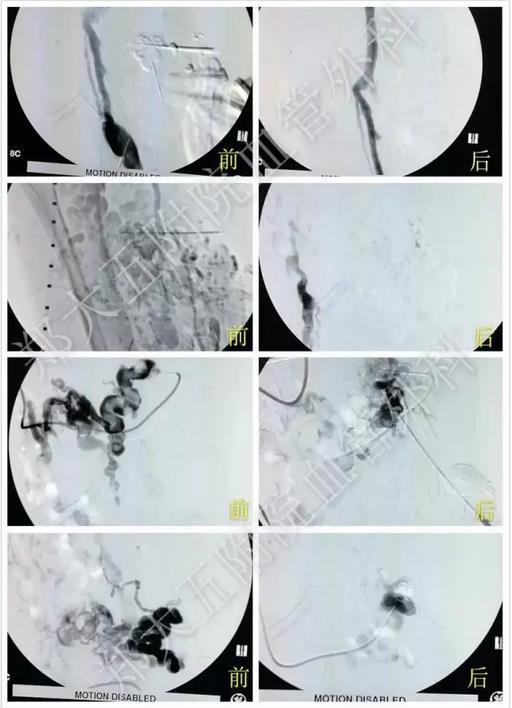

动脉造影结果证实了医生们的判断,确诊为Parkers-Weber综合征。手术过程中需要无水乙醇治疗,极易发生严重的心血管反应,但在手术麻醉科的强大技术保障下,平稳度过难关,手术顺利完成。

动脉造影证实左下肢确实存在动静脉瘘,证实为Parkers-Weber综合征

无水乙醇治疗,畸形血管团消失